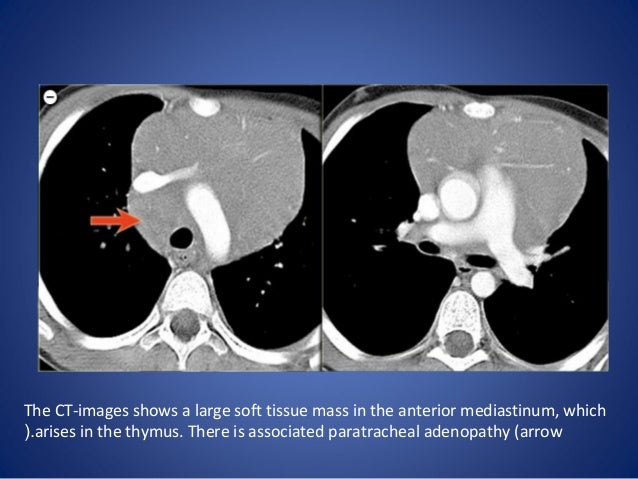

Clinical And Imaging Findings Useful In The Differential Diagnosis Of Most Common Childhood Mediastinal Tumors